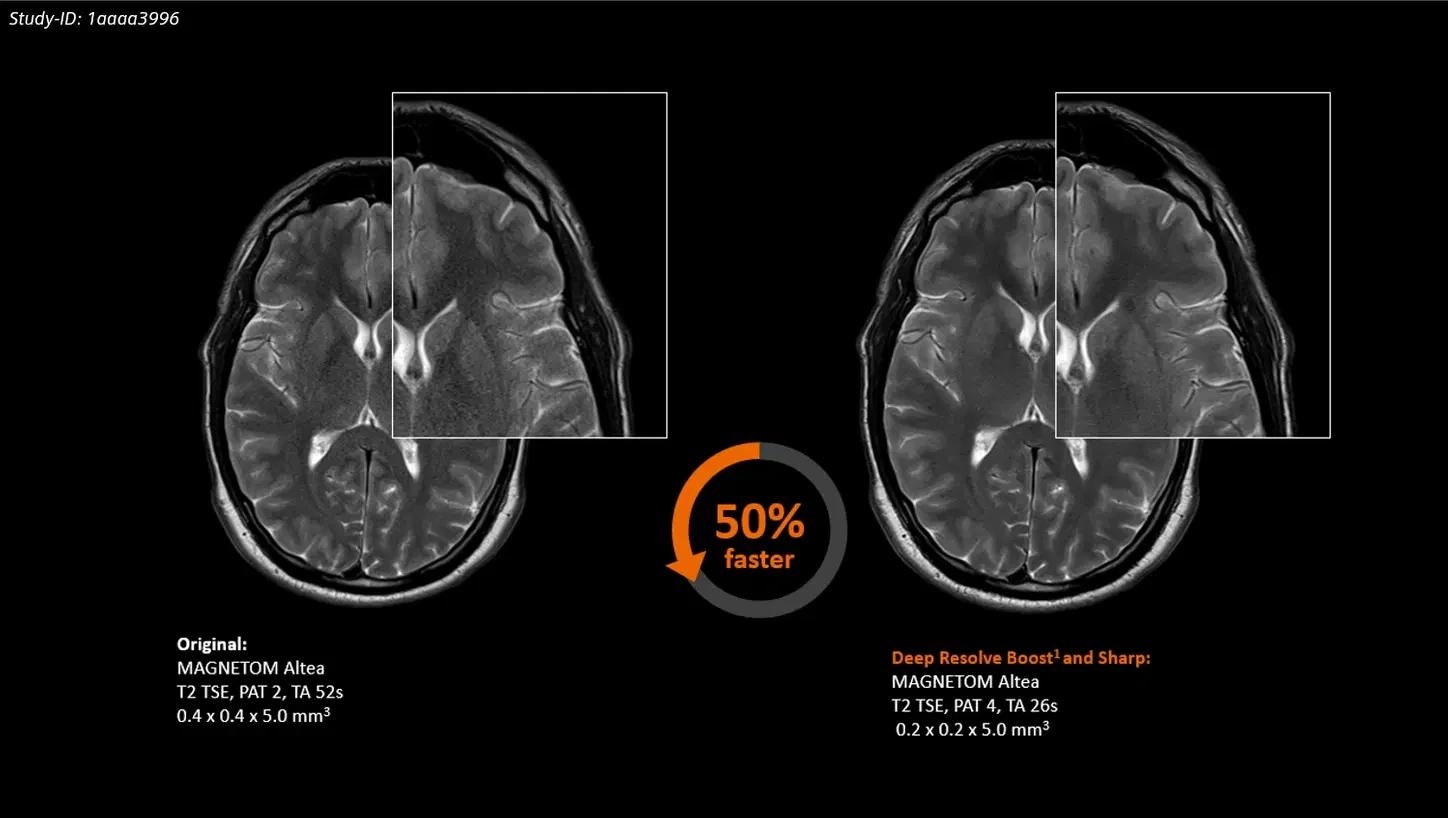

Deep Resolve Boost

Deep Resolve Boost is the first raw data-to-image deep learning reconstruction solution, allowing for high SNR and dramatically faster image capture.

Deep Resolve

Deep Resolve is an AI-powered image reconstruction technology that speeds up MR scans to record-breaking speeds.

Turbo Suite acceleration packages allow for up to 50%1 faster clinical routine examinations.

MAGNETOM Altea is designed with productivity sown into its DNA. The innovative and revolutionary acceleration technology Deep Resolve, an AI-powered image reconstruction tool that uses convolutional neural networks, is one outstanding component. MAGNETOM Altea, in conjunction with Turbo Suite and its acceleration techniques, accomplishes the goal of lowering overall patient slot times.